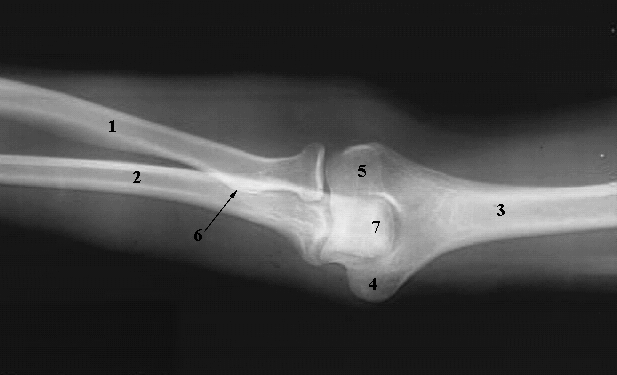

Upper Limbs: Elbow Extended:

1. Radial Shaft

2. Ulnar Shaft

3. Humeral Shaft

4. Medial Epicondyle

5. Lateral Epicondyle

6. Radial Tuberosity

7. Olecranon Process of the Ulna.